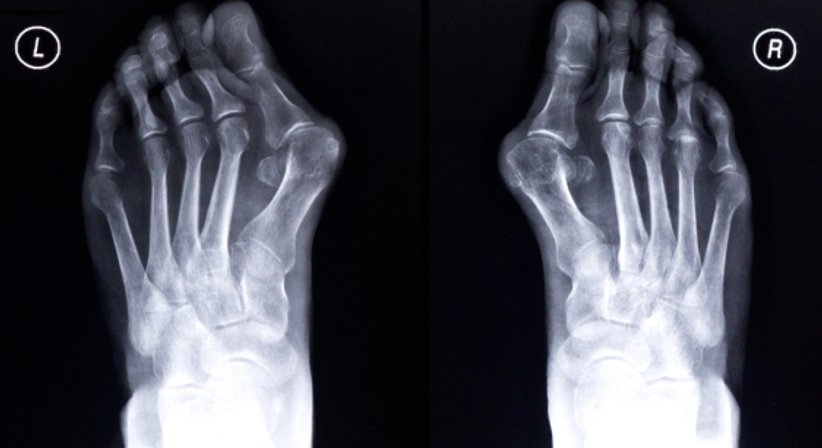

Hallux valgus

Hallux valgus, die häufigste Fehlstellung der Zehen, beschreibt eine Fehlstellung der Großzehe, bei welcher diese nach außen und damit in Richtung der anderen Zehen abweicht. Für viele Betroffene, zumeist Frauen, ist die Fehlstellung der Großzehe zunächst nur ein ästhetisches Problem, mit fortschreitendem Verlauf kann es allerdings zu teils starken Schmerzen kommen.

Das Grundgelenk der Großzehe schiebt sich zunehmend nach außen, wodurch sich eine Wölbung bildet. Oft findet sich eine Rötung oder Entzündung des hervorstehenden Köpfchens der Großzehe. Zusätzlich verdickt sich oft der Schleimbeutel im Zehenballenbereich, was zu Schwellungen und weiteren Schmerzen beitragen kann. Bei Nichtbehandlung schreitet die Erkrankung fort, die Großzehe schiebt sich über oder unter die kleinen Zehen und beeinträchtigt diese mit. Durch die veränderte Stellung trägt die Großzehe beim Abrollen nicht mehr die Belastung wie bei einem gesunden Fuß; Schmerzen beim Abrollen des Fußes können die Folge sein. Aufgrund der Schwächung der Großzehenfunktion müssen die benachbarten Mittelfußknochen der Kleinzehen die Belastung übernehmen. Schließlich kann es zu einer Überbelastung der kleinen Zehnen, Mittelfußschmerzen, einer veränderten Lastenverteilung auf der Fußsohle, Veränderungen des Gangbildes und einer Reihe weiterer Beschwerden wie auch anderen Fehlstellungen kommen. Unbehandelt kann ein Hallux valgus die gesamte Biomechanik des Fußes beeinträchtigen.